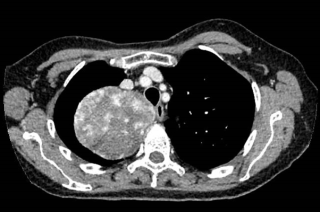

A 31-year-old previously healthy woman, with no surgical history, presented with sudden-onset, severe peri-umbilical abdominal pain unresponsive to high-dose opioids. CT-scan revealed mildly dilated distal jejunum with mesenteric edema and free fluid (Fig. 1, 2). Because of persistent pain despite step III analgesia, emergency diagnostic laparoscopy was performed. Intraoperatively, a closed-loop obstruction of an ileal segment was identified, herniated through a narrow internal window formed by an adherent mesenteric vessel supplying a Meckel’s diverticulum (Fig. 3). The vascular band was divided, releasing the closed loop, with no irreversible small bowel ischemic damage. The Meckel’s diverticulum was resected. The post-operative course was uneventful, and the patient was discharged after two days.

A 37-year-old man with an history of cirrhosis and atrial fibrillation treated with apixaban was admitted for weakness and dizziness. On admission, he was hypotensive and tachycardic, with signs of peripheral hypoperfusion and diffuse abdominal tenderness. Laboratory investigations revealed severe anemia (Hb 46 g/L), marked coagulopathy, and metabolic acidosis with elevated lactate levels. Abdominal CT scan demonstrated a left flank mesenteric lesion exerting mass effect on adjacent small bowel loops, associated with a large-volume acute hemoperitoneum. Emergency exploratory laparotomy revealed approximately 4 liters of hemoperitoneum and a large jejunal intramural hematoma with complete serosal rupture. Segmental jejunal resection was performed with temporary abdominal closure. A planned second-look laparotomy allowed jejunojejunal anastomosis. Histopathological examination confirmed a submucosal hematoma with preserved mucosa and no evidence of ischemia.